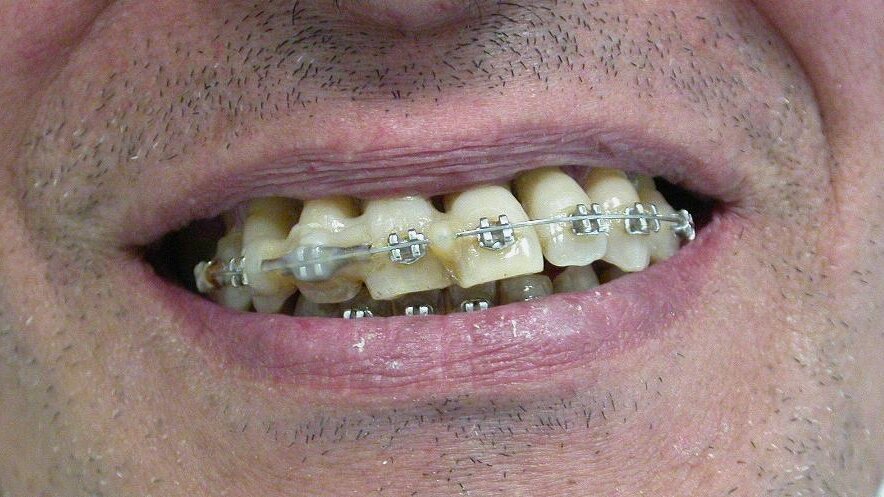

Iniziano le terapie (ablazioni tartaro, ortodonzia, scaling e root planing, curettages gengivali, farmaci nelle tasche, laser, test microbiologici ripetuti e trattamenti endocanalari) che si protraggono da febbraio 2012 al maggio 2015. Costo? Circa 11.500 euro, ma inizialmente i risultati ci sono: il paziente sta meglio, l’alitosi si ridimensiona, i denti perdono l’iniziale mobilità e si sono rapidamente allineati, anche se il livello di igiene domiciliare non è proprio migliorato.

Poi, però, la situazione cambia: i denti si sventagliano, alcuni risultano avulsi dagli alveoli (12, 22, 15, 25) restano in bocca solo perché attaccati al filo ortodontico. Altri si muovono più di prima. Poi qualche dente viene spontaneamente “sputato”. Il dottore da la colpa alla scarsa igiene domiciliare e propone alcune estrazioni (12, 22, 15, 25), interventi di chirurgia parodontale, altra endodonzia e protesi, con ulteriore richiesta di € 15 mila euro.

Alla visita del CTU le condizioni cliniche sono peggiori di quelle oggettivate (Figg. 1-4) alla fine del rapporto. Il riconoscimento di concorrenza di cause porta ad accollare a YZ solo parte dei danni rilevati (danno biologico 1% e ITP al 10% per 50 giorni), ma l’inadempimento fa riconoscere anche l’obbligo di rendere quanto percepito per prestazioni inutili e non indicate. Dovrà quindi restituire di tasca propria competenze per almeno 10.000 euro oltre alla franchigia prevista dal contratto di polizza in materia di risarcimento e alle spese legali. Nelle incaute promesse il Giudice riconosce, inoltre, un grosso vizio di consenso.